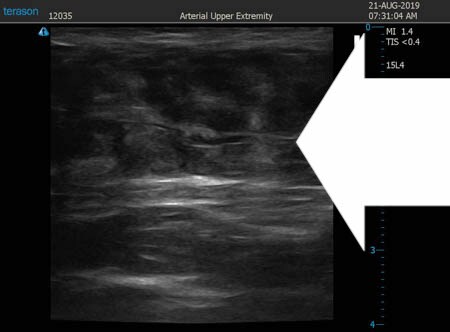

いつものように3Dタッチビュー(超音波)で

皮下脂肪層を評価してみましょう。

上腹部

↓ ↓ ↓